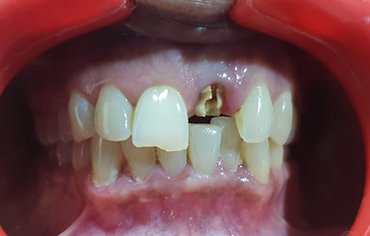

Missing teeth can significantly impact your confidence and overall appearance, making it difficult to achieve a perfect smile. Gaps in your teeth not only affect aesthetics but also lead to issues like difficulty in chewing, speech problems, and even jawbone deterioration over time. Fortunately, modern dental solutions like implants provide a permanent and natural-looking replacement. If you're looking for an Implant Center in Manjeri, you can get expert care and advanced treatment options to restore your smile seamlessly.